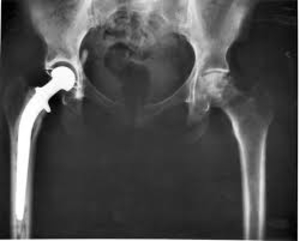

Hip Replacement surgery in Pune

Hip Replacement Hip replacement surgery is a operation where a damaged hip joint is replaced with a prosthetic. This surgery is helpful for people ...

Hip Replacement Surgery Pune

Hip Replacement Surgeon in Pune

Are you looking for Hip Replacement surgeon in Pune? Hip joint the largest and most important joint. We use this joint day in and day out while s...